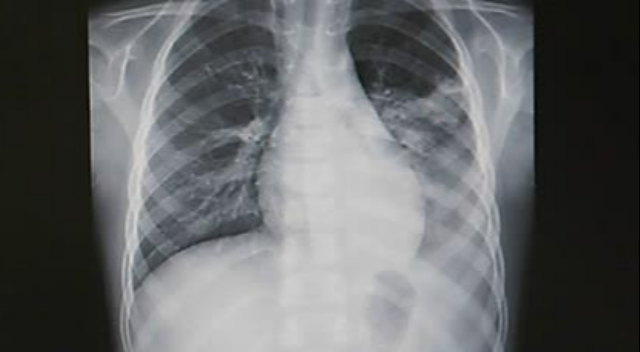

폐렴은 주로 세균성 또는 바이러스성 감염에 의해 유발되는 폐의 염증성 질환으로 대부분 2~4주 내에 호전된다. 그러나 영아, 고령자, 심장 또는 폐 질환 환자 등 취약 집단은 중증으로 진행될 위험이 높다.

폐렴의 주요 증상으로는 노란색 또는 녹색 점액(가래)을 동반할 수 있는 지속적인 기침, 숨 가쁨 및 흉통, 쌕쌕거리는 숨소리, 고열, 몸살, 극심한 피로감, 일시적인 식욕 부진 등이 대표적이다.

한편 세계보건기구(WHO)는 2~11개월 영아의 분당 호흡수 50회 이상, 1~5세의 40회 이상을 폐렴 가능성으로 본다. 여기에 갈비뼈 아래가 안쪽으로 들어가는 흉벽 함몰, 숨 쉴 때 끙끙거리거나 비정상적인 호흡음, 젖·물·식사 거부, 축 처진 의식 상태, 청색증 등이 동반되면 즉시 응급평가가 필요하다.

그러나 영아 폐렴은 이런 전형적 징후 없이도 진행될 수 있다. 단순 감기처럼 보이는 열, 반복 구토, 평소보다 심한 피로감, 잠만 자려는 행동, 혹은 부모가 가슴에서 느끼는 이상한 숨소리 같은 비특이적 변화가 초기 신호일 수 있다.